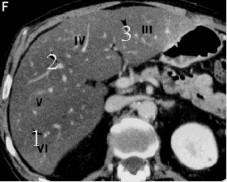

1.1.4. Phân chìa thùy và phân thùy gan trên CLVT:

Sự phân chia thuỳ và hạ phân thuỳ gan trên CLVT cũng dựa trên các mốc mạch máu đó là các tĩnh mạch gan và các nhánh phải và trái của tĩnh mạch cửa, các mặt phẳng tưởng tượng đi qua các mạch máu trên giúp phân biệt vị trí các thuỳ và phân thuỳ gan. Mặt phẳng qua TM gan phải chia gan phải thành phân thuỳ trước và sau. Mặt phẳng qua TM gan giữa chia gan thành gan phải và trái. Mặt phẳng qua TM gan trái chia gan trái thành thuỳ vuông và thuỳ đuôi. Mặt

phẳng ngang đi qua nhánh phải và trái phân chia các HPT trên gồm II, IVa, VII, VIII với các HPT dưới gồm III, IVb, V, VI [11].

Hình 1.5: Lớp cắt qua phần thấp của gan qua các HPT III, IVb, V, VI [11].